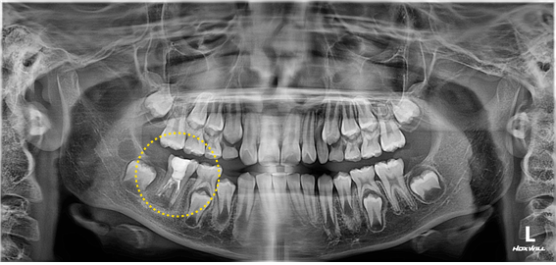

치료 전 단계입니다.

치근단유도술의 흔적은 없습니다.

이미 내부 신경은 괴사가 됐다고 판단하고, pulpectomy 시행하기로 합니다.